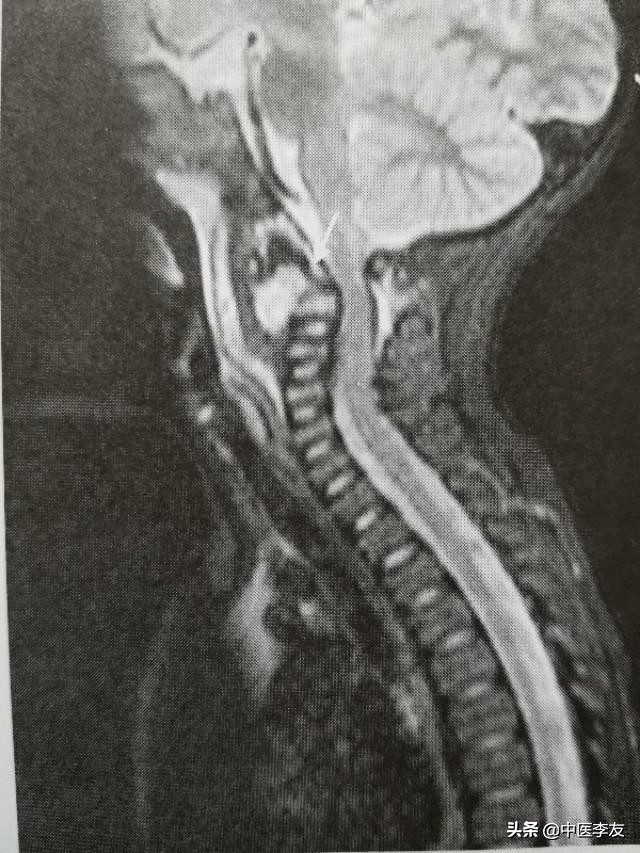

①颈椎:农业将突破椎体前方的骨膜和前中韧带废弃在颈长期以及其筋膜后方,第四颈椎以上可能形成咽后壁脓肿,第五颈椎以下可能形成食管后脓肿压迫喉头和食管,造成呼吸与吞咽困难。颈椎侧方病变的脓肿可出现在颈部两侧,或者沿着椎前的筋膜,以久斜方肌向锁骨上窝流窜。

3.MRI,表现是显示脊椎结核病灶和范围最敏感的方法,可发现椎体内早期炎性水肿。病灶T1WI表现为低信号,T2WI多表现为混杂高信号;GD-DTPA增强不均匀强化。脓肿和肉芽肿在T1WI上呈低信号,T2WI多为混杂高信号,部分均匀高信号,增强检查肉芽肿不均匀,均匀强化,脓肿壁薄且均匀的环状强化。

脊柱结核患者中截瘫的发生率在10%左右,胸椎结核发生截瘫的最多,颈椎次之,颈胸段第三。椎弓结核较少见,但因椎弓从三面环绕椎管,故并发截瘫的比例较高。

脊柱结核并发截瘫的原因,可分为骨病变活动型结核和骨病变静止型截瘫。前者在结核早期或活动期由于脓肿、干酪样物质、肉芽组织、坏死的椎间盘直接压迫脊髓所致。后者在晚期或病变愈合期,由增厚的硬膜、椎管内肉芽组织纤维化及纤维组织增生,脊柱后凸畸形或椎体病理性移位压迫脊髓。此外,脊髓血管发生栓塞导致脊髓变性、软化,也可发生截瘫。